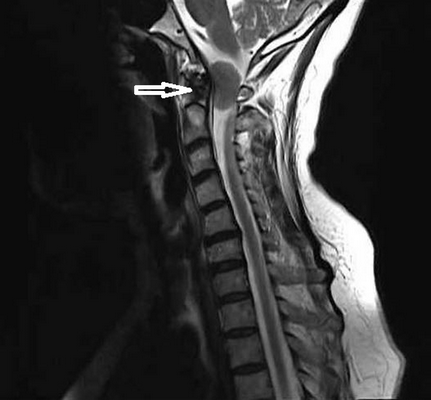

(Слева) Этот сагиттальный КТ-срез иллюстрирует передний подвывих мыщелка затылочной кости относительно С1. Видны свободно лежащие небольшие фрагменты мыщелка.

(Справа) Т2-ВИ, сагиттальная проекция: выраженные изменения связочного аппарата КВС, истончение и нарушение непрерывности текториальной мембраны. Передняя атланто-затылочная мембрана неправильной формы и натянута кпереди. Аномальный гипоинтенсивный сигнал от мягких тканей в надзубовидной области позволяет заподозрить повреждение апикальной, крыловидной и связки Баркова.